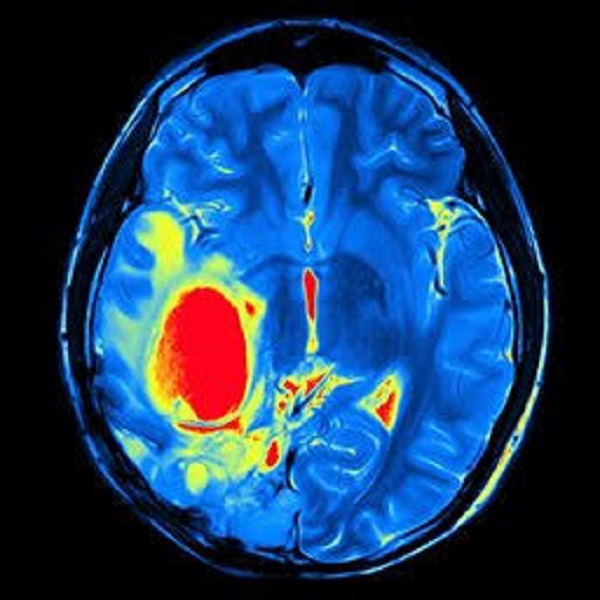

Beyin Tümörleri

Beyin tümörleri sık görülen tümörler değildir. Beyinde sinir hücrelerinin yanı sıra bağ dokusu hücreleri ve beyin zarını oluşturan hücreler de vardır. Tümörler beyin dokusunu (nöronal ve glial) veya onu çevreleyen beyin zarını (meningial) oluşturan hücrelerden köken alabilir. Beyin tümörleri bu nedenle çok heterojen özellik gösterirler. Bir kısmı iyi huyludur, bazıları kötü huylu davranış gösterir.

Beyin tümörü teşhisi

Şüphe olan hastalarda beyin tomografisi (BT) veya tercihen kontrastlı beyin manyetik rezonans görüntüleme (MR) ile tanı konur. Kan tetkiklerinde genellikle bir anormallik yoktur. Cerrahiye uygun olmayan tümörlerde biyopsi yapılmalıdır. Tanı koymak için stereotaksik biyopsi ile örnek alınmalıdır. Özellikle derin yerleşimli tümörlerde ya da yaygın beyin tutulumu olan hastalarda BT veya MR ile işaretleme sonrası kafatasına açılan küçük bir delikten ince bir iğne ile girilerek tümör dokusundan örnek alınır. Cerrahiye uygun ise tanı ve tedavi aynı anda cerrahi olarak yapılabilir.